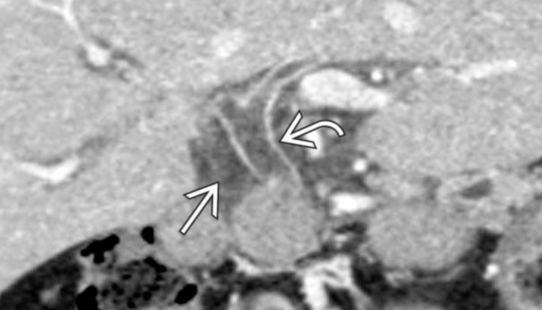

- Prise de contraste des VB

- Oedème des VB

- Dilatation des VB

- Pus (hyposignal IRM, hyperdense CT)

- Obstruction (calcul, etc…)

Pus en hyposignal T2